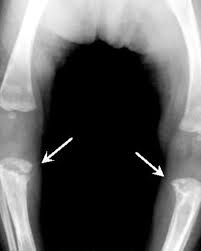

Wimberger’s Sign

Wimberger’s sign refers to localized bone destruction or demineralization of the medial aspect of the proximal tibial metaphysis. It is often considered a radiological finding suggestive of congenital syphilis in infants. This condition occurs due to the involvement of rapidly growing bones in syphilitic periostitis or osteitis.

- Cause: Congenital syphilis (usually secondary to spirochetal infection transmitted from the mother to the fetus).

- Appearance: Bilateral, symmetrical defects in the medial portion of the proximal tibial metaphysis.

- Differential Diagnosis: Other conditions, such as rickets or scurvy, may cause bone deformities, but the symmetry and specific localization are more characteristic of congenital syphilis.